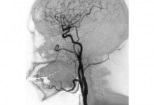

Angiografie

Ce este angiografia / coronarografia? Angiografia este o interventie non-chirurgicala minim invaziva, nedureroasa, ce se efectueaza cu ajutorul razelor X si permite vizualizarea aspectului intern al vaselor de sange ale membrelor, organelor interne sau inimii.Coronarografia sau angiografia coronariana, este cea mai buna tehnica de diagnosticare a afectiunii coronariene. Ceea ce trebuie sa retinem